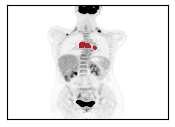

There has been growing research interest in using deep learning based method to achieve fully automated segmentation of lesion in Positron emission tomography computed tomography(PET CT) scans for the prognosis of various cancers. Recent advances in the medical image segmentation shows the nnUNET is feasible for diverse tasks. However, lesion segmentation in the PET images is not straightforward, because lesion and physiological uptake has similar distribution patterns. The Distinction of them requires extra structural information in the CT images. The present paper introduces a nnUNet based method for the lesion segmentation task. The proposed model is designed on the basis of the joint 2D and 3D nnUNET architecture to predict lesions across the whole body. It allows for automated segmentation of potential lesions. We evaluate the proposed method in the context of AutoPet Challenge, which measures the lesion segmentation performance in the metrics of dice score, false-positive volume and false-negative volume.